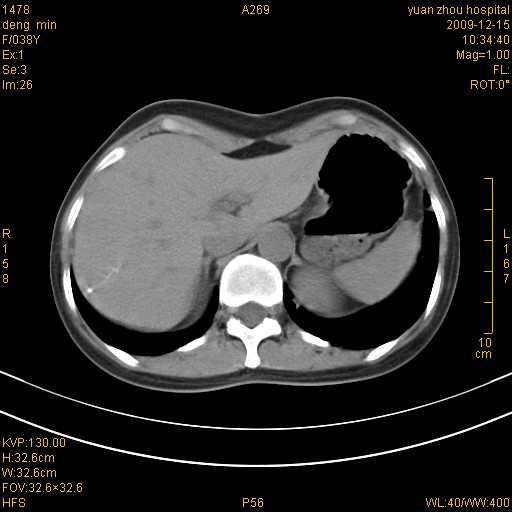

标题: CT23919:F38Y 咳嗽月余 [打印本页]

标题: CT23919:F38Y 咳嗽月余

右肺中下叶、左肺上叶舌段及左肺下叶支气管扩张合并感染。